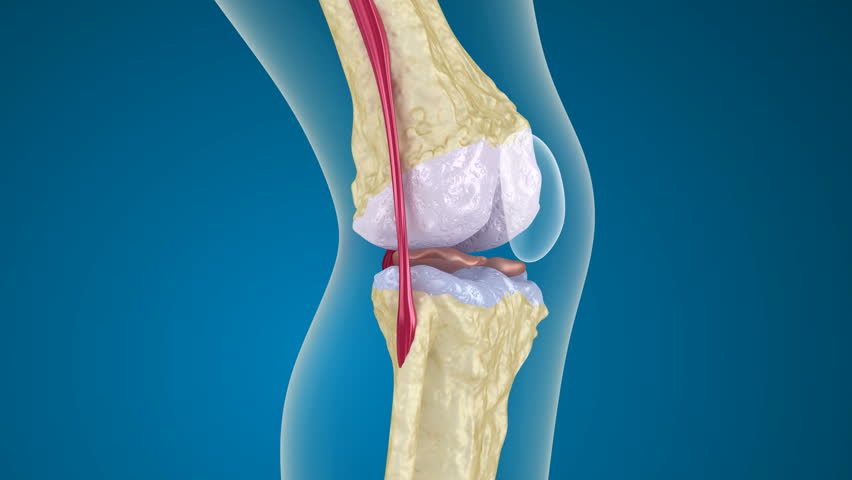

Медицинские снимки: рентген коленного сустава при остеопорозе